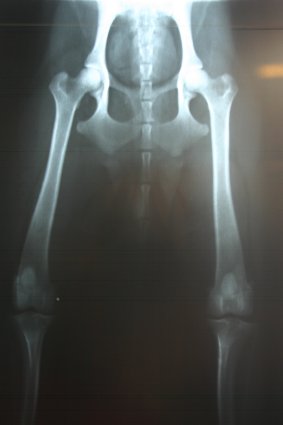

Dayen Röntgenaufnahme * HD-A